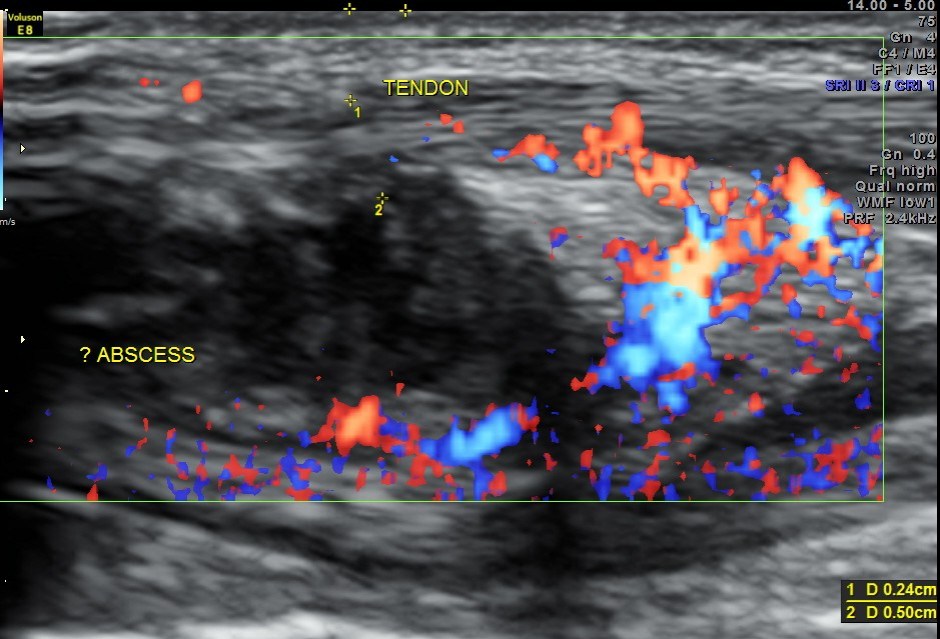

Ultrasound done with high resolution transducer revealed the following findings :

An indistinct hypo echoic mass was seen under a tendon and was well away from the surface of the bone .

Colour Doppler showed increased vascularity all around .

A diagnosis of an abscess in formation was offered and the child recovered well with appropriate treatment.

The following are the pictures.

This case is presented to illustrate how musculo skeletal ultrasound and colour Doppler can be very useful to assess soft tissue pathology.